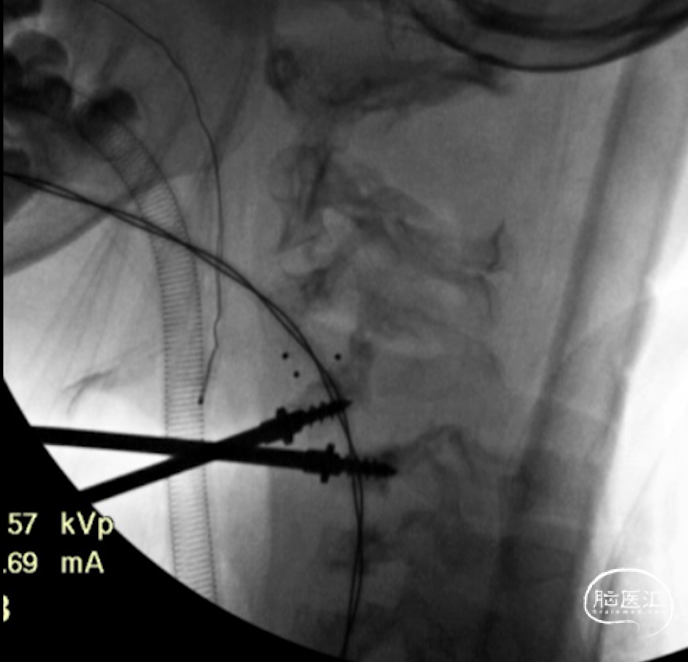

C4-5置入牵开钉,可见椎体只能容纳一个牵开钉宽度

C3-4,C4-5,C5-6融合器放置完成

上钢板及螺钉,显示C5椎体无法良好复位

C5椎体内置入提拉螺钉,穿透椎体后壁,达到最佳提拉复位力量

旋转提拉套筒,显示C5椎体进一步向前复位

C5复位后置换置入前路螺钉

前路手术完成后,翻身行后路C2-C7置钉

C4及C5侧块无法置钉,双侧C5放置椎板钩增加把持力